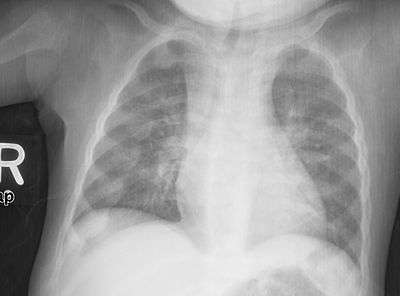

Rachitic rosary on chest radiograph

The prominent knobs of bone at the costochondral joints of rickets patients are known as a rachitic rosary or beading of the ribs. The knobs create the appearance of large beads under the skin of the rib cage, hence the name by analogy with the beads of a Catholic Christian rosary.[1]

Rachitic rosary is due to a deficiency of calcium resulting in lack of mineralization and an overgrowth of costochondral joint cartilage. The calcium deficiency may be caused by Rickets or other causes of calcium deficiency such as hypoparathyroidism.